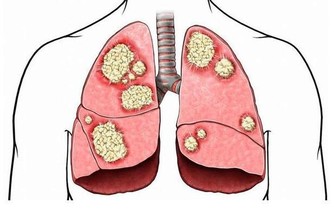

1.脂肪墊勞損 脂肪墊充填於膝關節前部的間隙,有加強關節穩定和減少摩擦的作用。脂肪墊勞損的發病原因可能是由於外傷或者是長期摩擦引起脂肪墊充血、肥厚並發生炎症,與髕韌帶發生粘連,從而使膝關節活動受限。這種損傷多發生於經常步行、登山或者蹲起運動較頻繁的30歲以上人群。患者會覺得膝關節疼痛,完全伸直時疼痛加重,但關節活動並不受到限制。勞累後症狀明顯。治療以保守治療為主,配合理療及口服藥物。 2.半月板損傷 半月板損傷是運動員的一種常見損傷,在下肢負重,足部固定,膝關節微屈時,如果突然過度內旋伸膝或外旋伸膝(例如排球運動中,隊員在防守時突然轉身魚躍救球的動作),就有可能引起半月板撕裂。半月板損傷會有明顯的膝部撕裂感,隨即關節疼痛,活動受限,走路跛行。關節表現出腫脹和滑落感,並且在關節活動時有彈響。治療需根據損傷程度決定保守治療還是手術治療。 3.膝關節創傷性滑膜炎 膝關節滑膜是組成膝關節的主要結構之一。滑膜細胞分泌滑液,可以保持關節軟骨面的滑潤,增加關節活動範圍。由於外傷或過度勞損等因素損傷滑膜,會產生大量積液,使關節內壓力增高,如不及時消除,則很容易引起關節粘連,影響正常活動。患者會感覺膝關節疼痛、腫脹、壓痛,滑膜有摩擦發澀的聲響。疼痛最明顯的特點是當膝關節主動極度伸直時,特別是有一定阻力地做伸膝運動時,髕骨下部疼痛會加劇,被動極度屈曲時疼痛也明顯加重。治療多以保守治療為主。 4.膝關節骨性關節炎 這種病症多見於中老年、女性居多,超重負荷是致病的主要原因。膝關節會腫脹而疼痛,有時活動關節會有摩擦音。膝部可能出現內翻畸形並伴有內側疼痛。治療根據關節蛻變情況選擇是否行關節置換的治療,目前膝關節骨性關節炎的關節置換治療是國際上較成熟的治療方式。 5.膝關節韌帶損傷 膝關節微屈時的穩定性相對較差,如果此時突然受到外力導致外翻或內翻,則有可能引起內側或外側副韌帶損傷。臨床上內側副韌帶損傷占絕大多數。以這種損傷為例,患者會有明確的外傷史,膝關節內側疼痛、壓痛,小腿被動外展時疼痛加劇,膝內側有腫脹,幾天後會出現瘀斑。膝關節活動會受到限制。 6.寒冷 在日常生活中,多數關節疼痛並不是由外傷引起的,寒冷(特別是持續受涼和巨大的溫度反差)才是造成關節疼痛的主要原因。隨著社會的發展,人們的審美觀、生活習慣發生了很大的變化,人們更加注重形態美。即使是在寒冷的冬季,很多人也不再身著厚厚的棉服,而是儘可能地減輕身上的負擔,以適應現代審美觀念及快速的生活節奏。但是在體驗美感的同時,人們不得不付出關節損害的代價,因為寒冷可導致肌肉和血管收縮,引起關節疼痛。 7.運動不當 有些老年人喜歡登山,但如果沒做好準備活動或運動量太大,也可造成關節疼痛。特別是身患關節滑膜炎或骨性關節炎的人,更容易引起關節疾病發作或加重。在登山運動中,下山時,全身的重量完全加在一側膝關節上,膝關節承受的壓力是正常站立時的數倍。人們上下樓梯時,也會出現同樣的情況。 8.不良走路習慣 例如經常穿著不合腳的鞋或穿著拖鞋、高跟鞋長距離行走,會使膝關節長時間處於非正常的受力狀態,造成膝關節慢性損傷,引起疼痛。 9.風濕,類風濕,強直性脊柱炎,紅斑狼瘡等免疫性疾病引起的膝關節病變。 10.代謝性疾病如「痛風」引起的膝關節疼痛發病率有明顯的上升趨勢。 #如常老年專用中藥熱敷包#